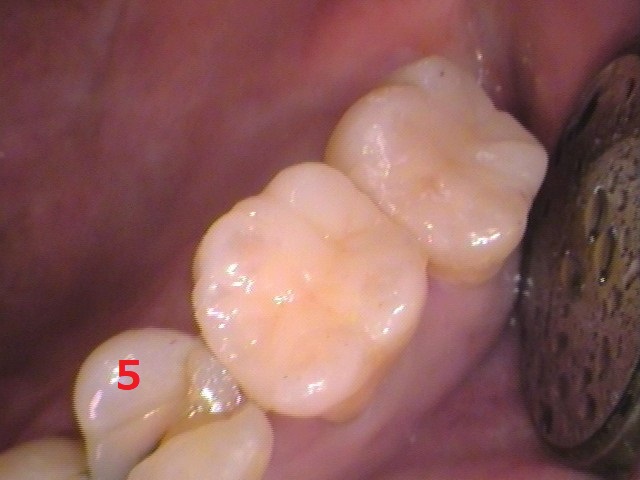

長くなりましたが、5番目の歯の治療です。

既に治療されていた、レジン(プラスチック樹脂)を削って内部を確認すると、

何やら黒い虫歯が出てきました。

セラミックをセットして終了です

歯の色を記録して、セラミックインレーを製作します。

後日、セラミックがセットされた状態です。

治療前と

治療後

やはり歯は白い方がいいですね(*^-^*)